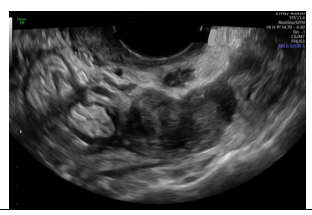

Paciente nulípara, sem uso de contraceptivos, comparece ao ginecologista com queixa de dispareunia e dismenorreia importantes, com piora cíclica no período menstrual. Apresenta a seguinte imagem ao exame de ultrassom endovaginal:

A imagem ecográfica sugere como diagnóstico